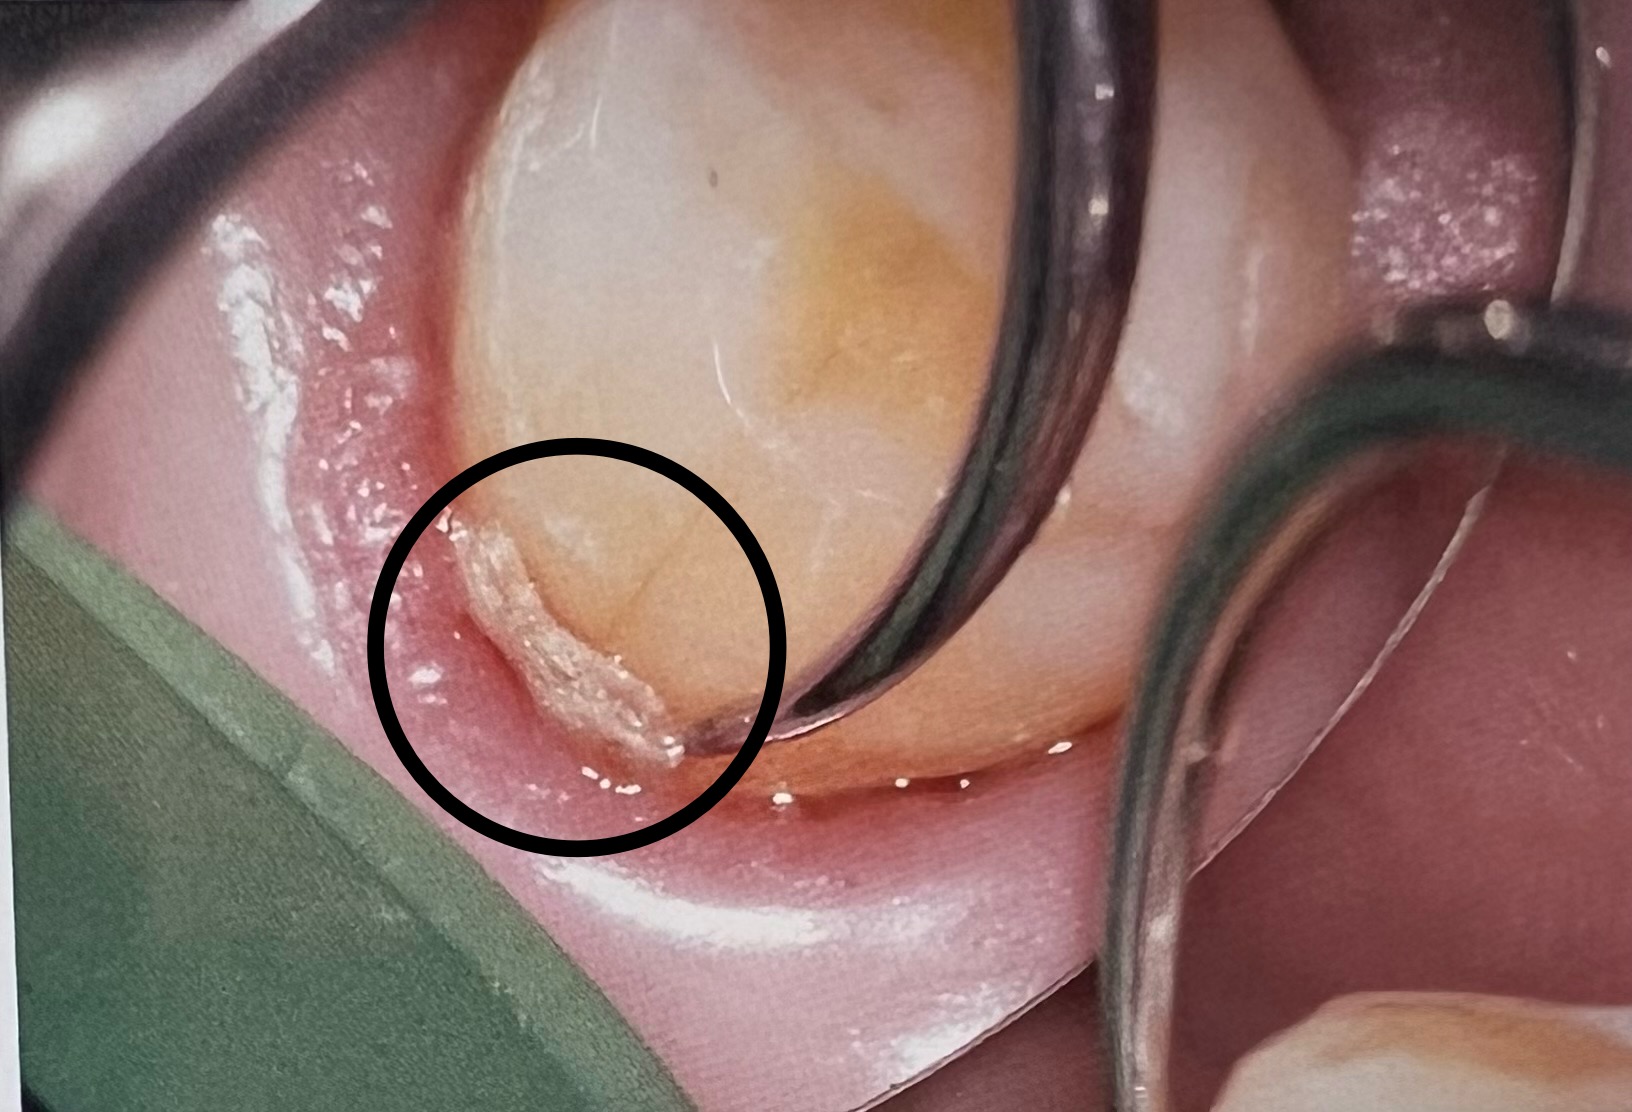

これは縁下歯石です。

超音波スケーラーを使って歯石を除去しています。

歯石を綺麗に除去できました✨

このようにマイクロスコープでは肉眼では見えづらい縁下歯石も目で見て確認しながら除去することができます‼️✨

下の段の写真は細い器具で歯肉溝を広げて確認をしたものです。歯肉溝の中には汚れが石灰化した塊が付着しています。

これは、歯肉の溝にできる縁下歯石というものです。